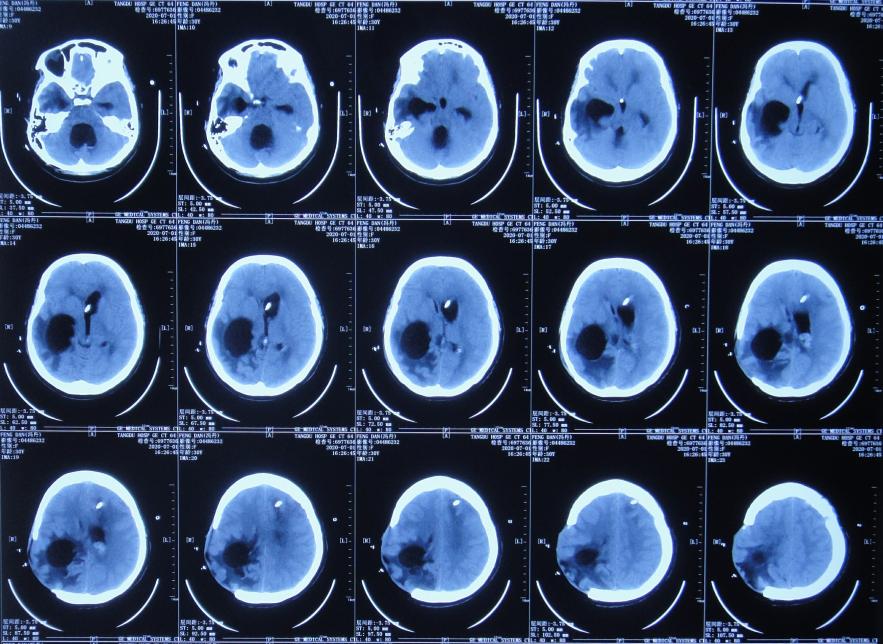

开颅术后次日即2020年4月3日,意识恢复,可简单言语,但左侧肢体偏瘫,仅可在床面平移,伴发热体温最高39.0℃;复查头颅CT示开颅术后去骨瓣状态,出血有减少,引流术后状态( 图-2 )。

图-2: 2020年4月3日头颅CT

开颅术后第3天即2020年4月5日,因出血明显减少,拔除了脑室外引流管( 图-3 )。

图-3: 2020年4月5日头颅CT